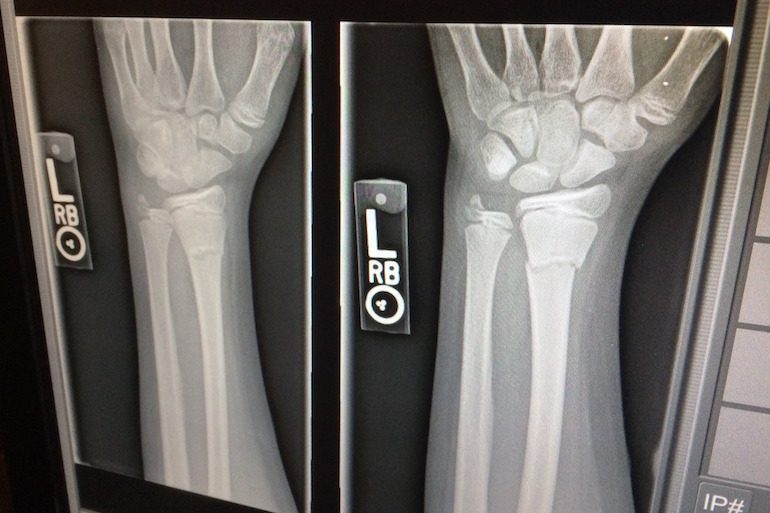

Cette fameuse discipline d’imagerie médicale et de médecine nucléaire traite de l’étude des rayons X et autres rayonnements ionisants. L’ensemble des techniques qui usent de rayonnements, à ne pas confondre avec la radiographie. La radiologie est utilisée dans différents domaines comme le suivi ou la découverte d’une maladie chez un patient, la destruction de cellules cancéreuses (radiothérapie), le repère de fractures, de lésions de toutes sorte comme l’arthrose ou anomalie vasculaire, ainsi que pour découvrir d’autres malformations.

La journée mondiale de la radiologie met également un point d’honneur sur tous les manipulateurs de rayons X, notamment tous ceux qui sont décédés à partir des année 1900 alors que l’on ne connaissait pas encore les dangers réels et mortels d’une surexposition aux rayons. Sans protection les premiers manipulateurs furent gravement brûlés et subirent l’apparition de cancers ou même l’amputation des doigts et des mains.